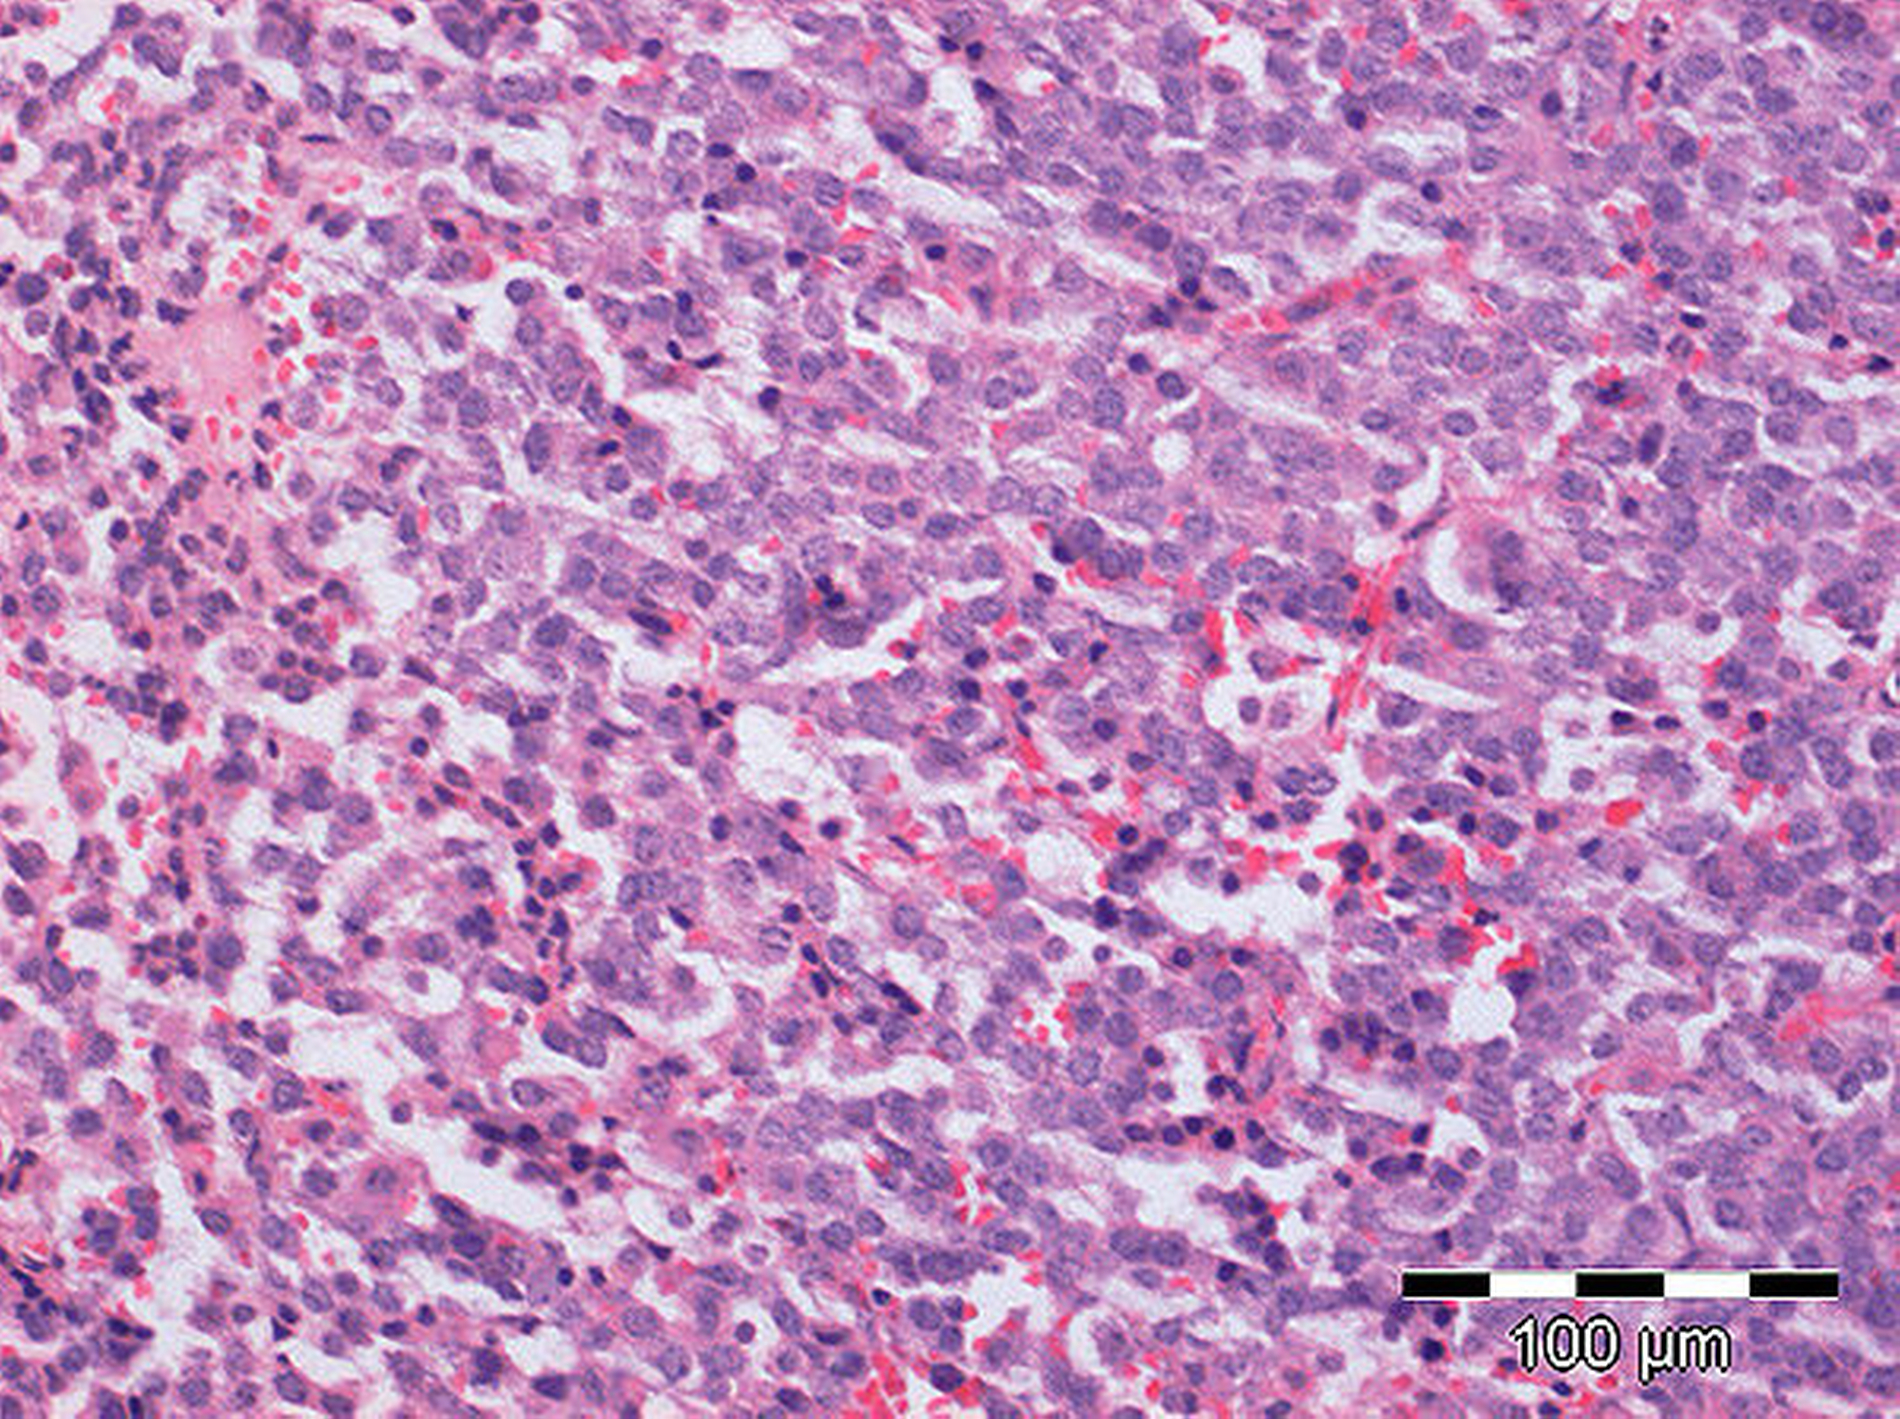

Aufgrund eines Liquorlecks wurde nach zwei Wochen eine Revisionsoperation erforderlich, wobei der Sellaboden mit Fascia lata vom rechten Oberschenkel abgedichtet wurde. Der histopathologische Untersuchungsbefund wies ein Hypophysenadenom mit Immunpositivität für STH sowie schwach für LH und Prolactin nach (Abbildung 4).